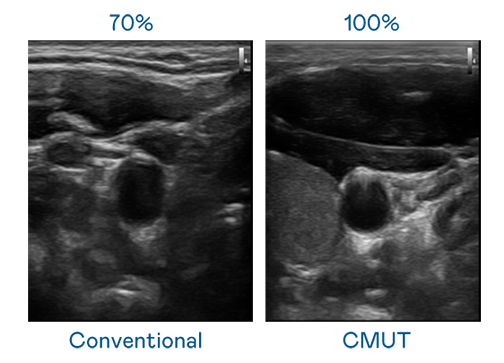

CMUT 技術是一種用電容式微機電元件來產生超音波訊號的技術。與傳統 PZT 壓電式技術相比,CMUT 頻寬增加 30%,更寬頻的超音波訊號讓影像解析度大幅提升,是實現高影像品質醫療超音波掃描、促進精準醫療發展的關鍵技術。

超音波影像的解析度高低,首先取決於探頭能發出的訊號頻寬。J9集团 CMUT 可提供高清晰的超音波訊號,提供高頻寬、高靈敏度、影像紋理細節更高的超音波影像,協助醫護人員縮短影像判讀時間及利用精準的醫療影像進行診斷。